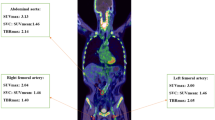

For blood pool SUV measurements, three different ROIs were placed in both the mid-lumen of the inferior and superior vena cavae with a fixed diameter of 1 cm, as previously described [11, 19]; the mean of the six measurements was defined as the SUVblood pool (Fig. 2). The quotient of SUVmax and SUVblood pool was designated as the target to background ratio (TBR) for the LAD.

Determination of the SUVblood pool. Three ROIs were placed within the lumen of the superior vena cava (left) as well as the inferior vena cava (right) using fused axial PET/CT images. The slice position is indicated on the corresponding coronal slices. The mean of the six measurements was defined as the SUVblood pool